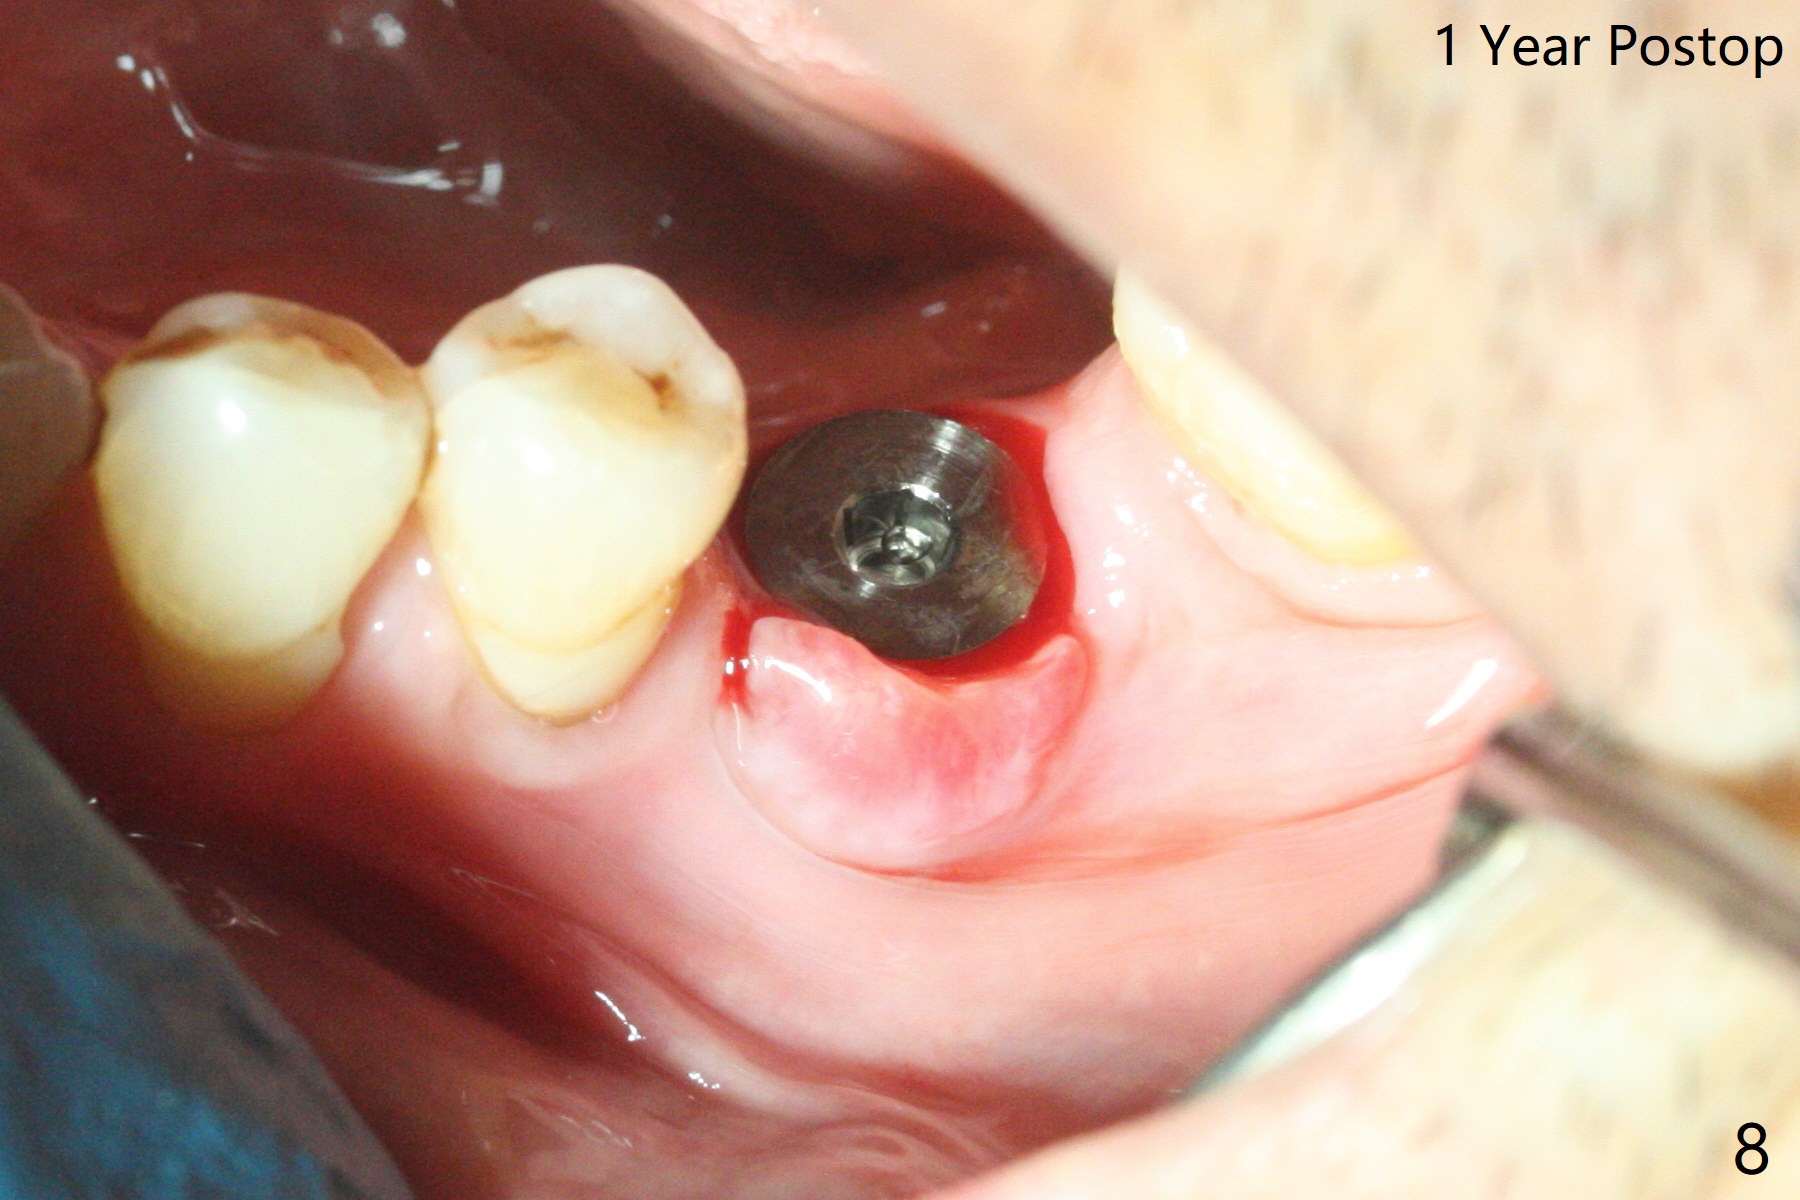

After 4.0x10 mm drill with 9 mm offset for 4.5x10 mm bone-level implant at #19, a 4.5x17 mm tissue level tap is inserted with apparently low torque (probably without reaching the depth). When a 4.5x14 mm tissue level implant is placed with high torque, a 4.5x7.3 mm drill is used for ~ 6.5 mm. The implant loses the primary stability with over-insertion (Fig.1). When an abutment is placed, the implant is critically loose. Mixture of autogenous bone, Osteogen and allograft is placed in the osteotomy. The implant regains stability with better placement level for restoration (Fig.2). In fact the bone density around the implant increases (Fig.2 *). For the first 7 days postop, the patient has to take Advil. When he returns for follow up 8 days postop (Fig.3), the pain decreases, while there is minor degree of lower lip paresthesia. Medrol Dose Pak and Tylenol III are prescribed. The implant is loose 24 days postop; after removal of the implant and apparently infected bone graft, a 7x14 mm dummy implant is inserted with <20 Ncm and 3-4 mm clearance (Fig.4). A longer dummy implant seems to improve stability (Fig.5). So does the definitive implant (Fig.6,7, 25 Ncm), but it is placed low. The gingiva looks healthy 13 days postop (2nd placement). A healing cap will be placed for restoration ~ 3 months postop. CT will be taken if the implant needs to be backed up to determine whether there is enough bone buccolingually. Due to coronavirus and prolonged placement of a healing abutment with poor oral hygiene, the buccal gingiva of the implant is erythematous 1 year postop (Fig.8 healing cap just removed) with bone loss (Fig.9,10 *). Sticky bone seems to be necessary. A 6x5 mm abutment with slots will be placed to hold periodontal dressing in place.